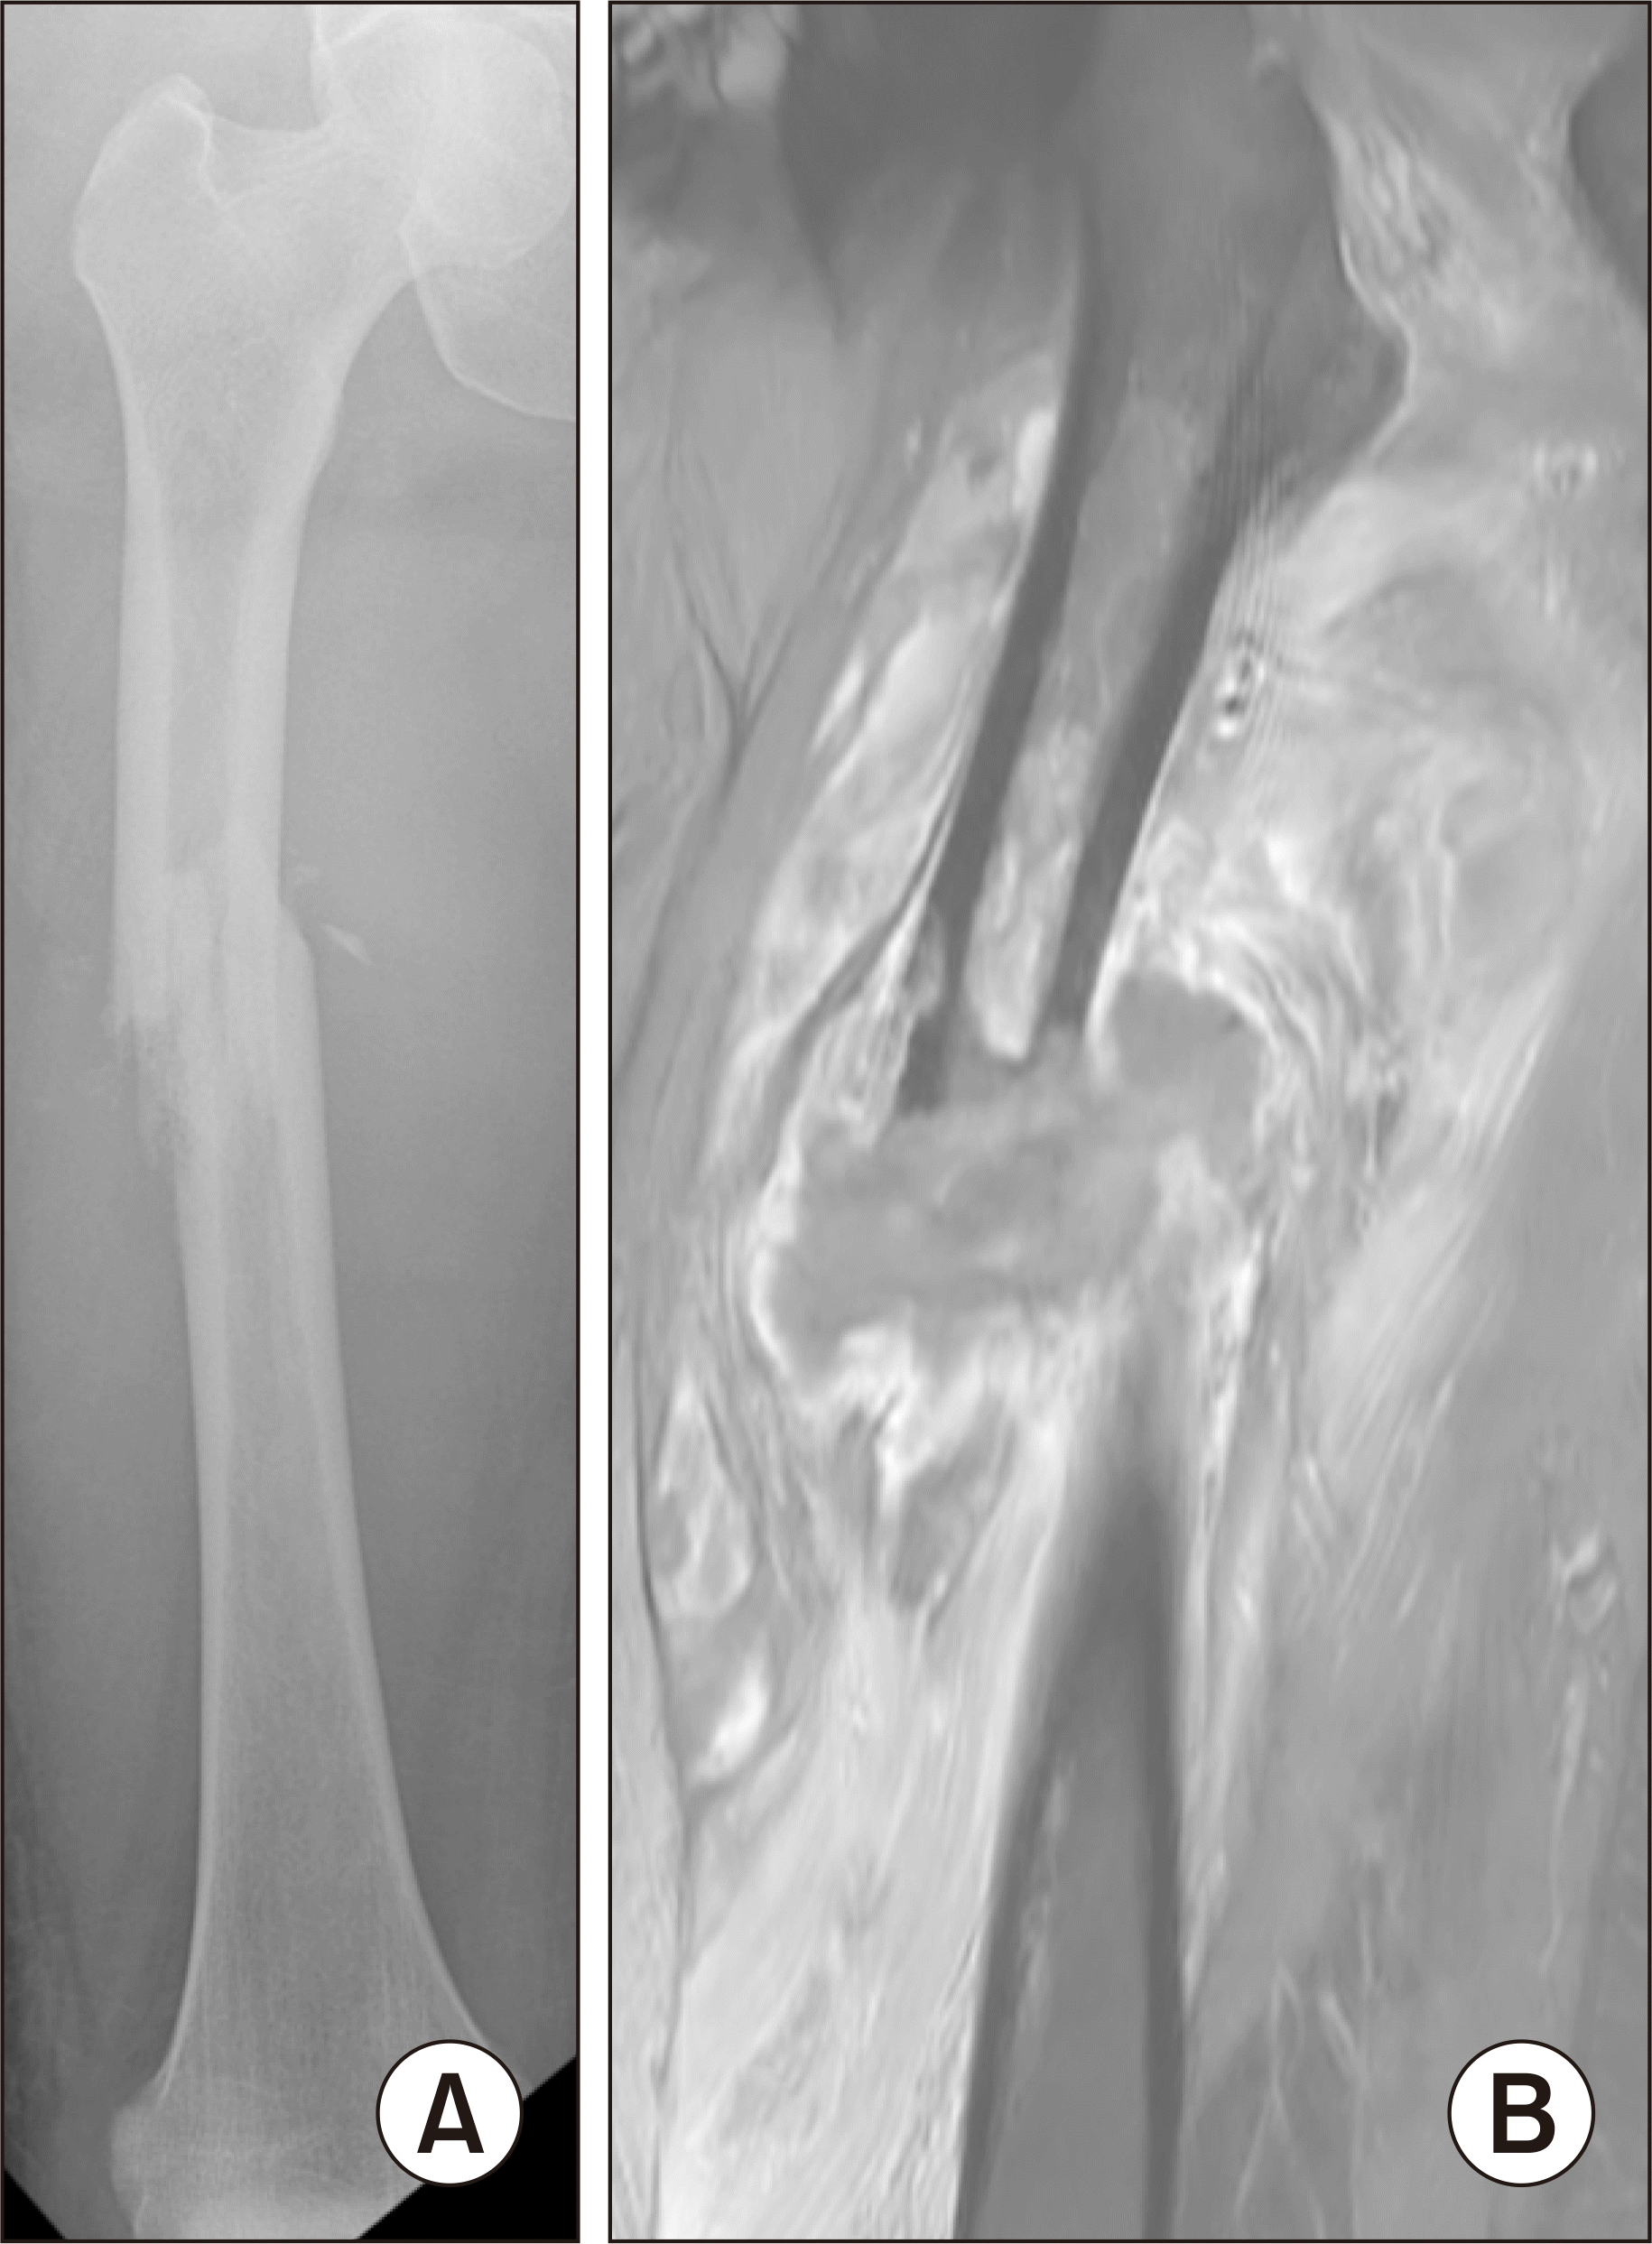

Figure 4

(A) The three-phase bone scan shows positive uptake on the flow, blood pool and delayed phases on the left distal femur shaft and entire tibia and right femur shaft. (B) The enhanced magnetic resonance imaging of the left tibia shows whole tibia osteomyelitis and abscess pocket in subcutaneous and fascia layer of anterior lower leg.